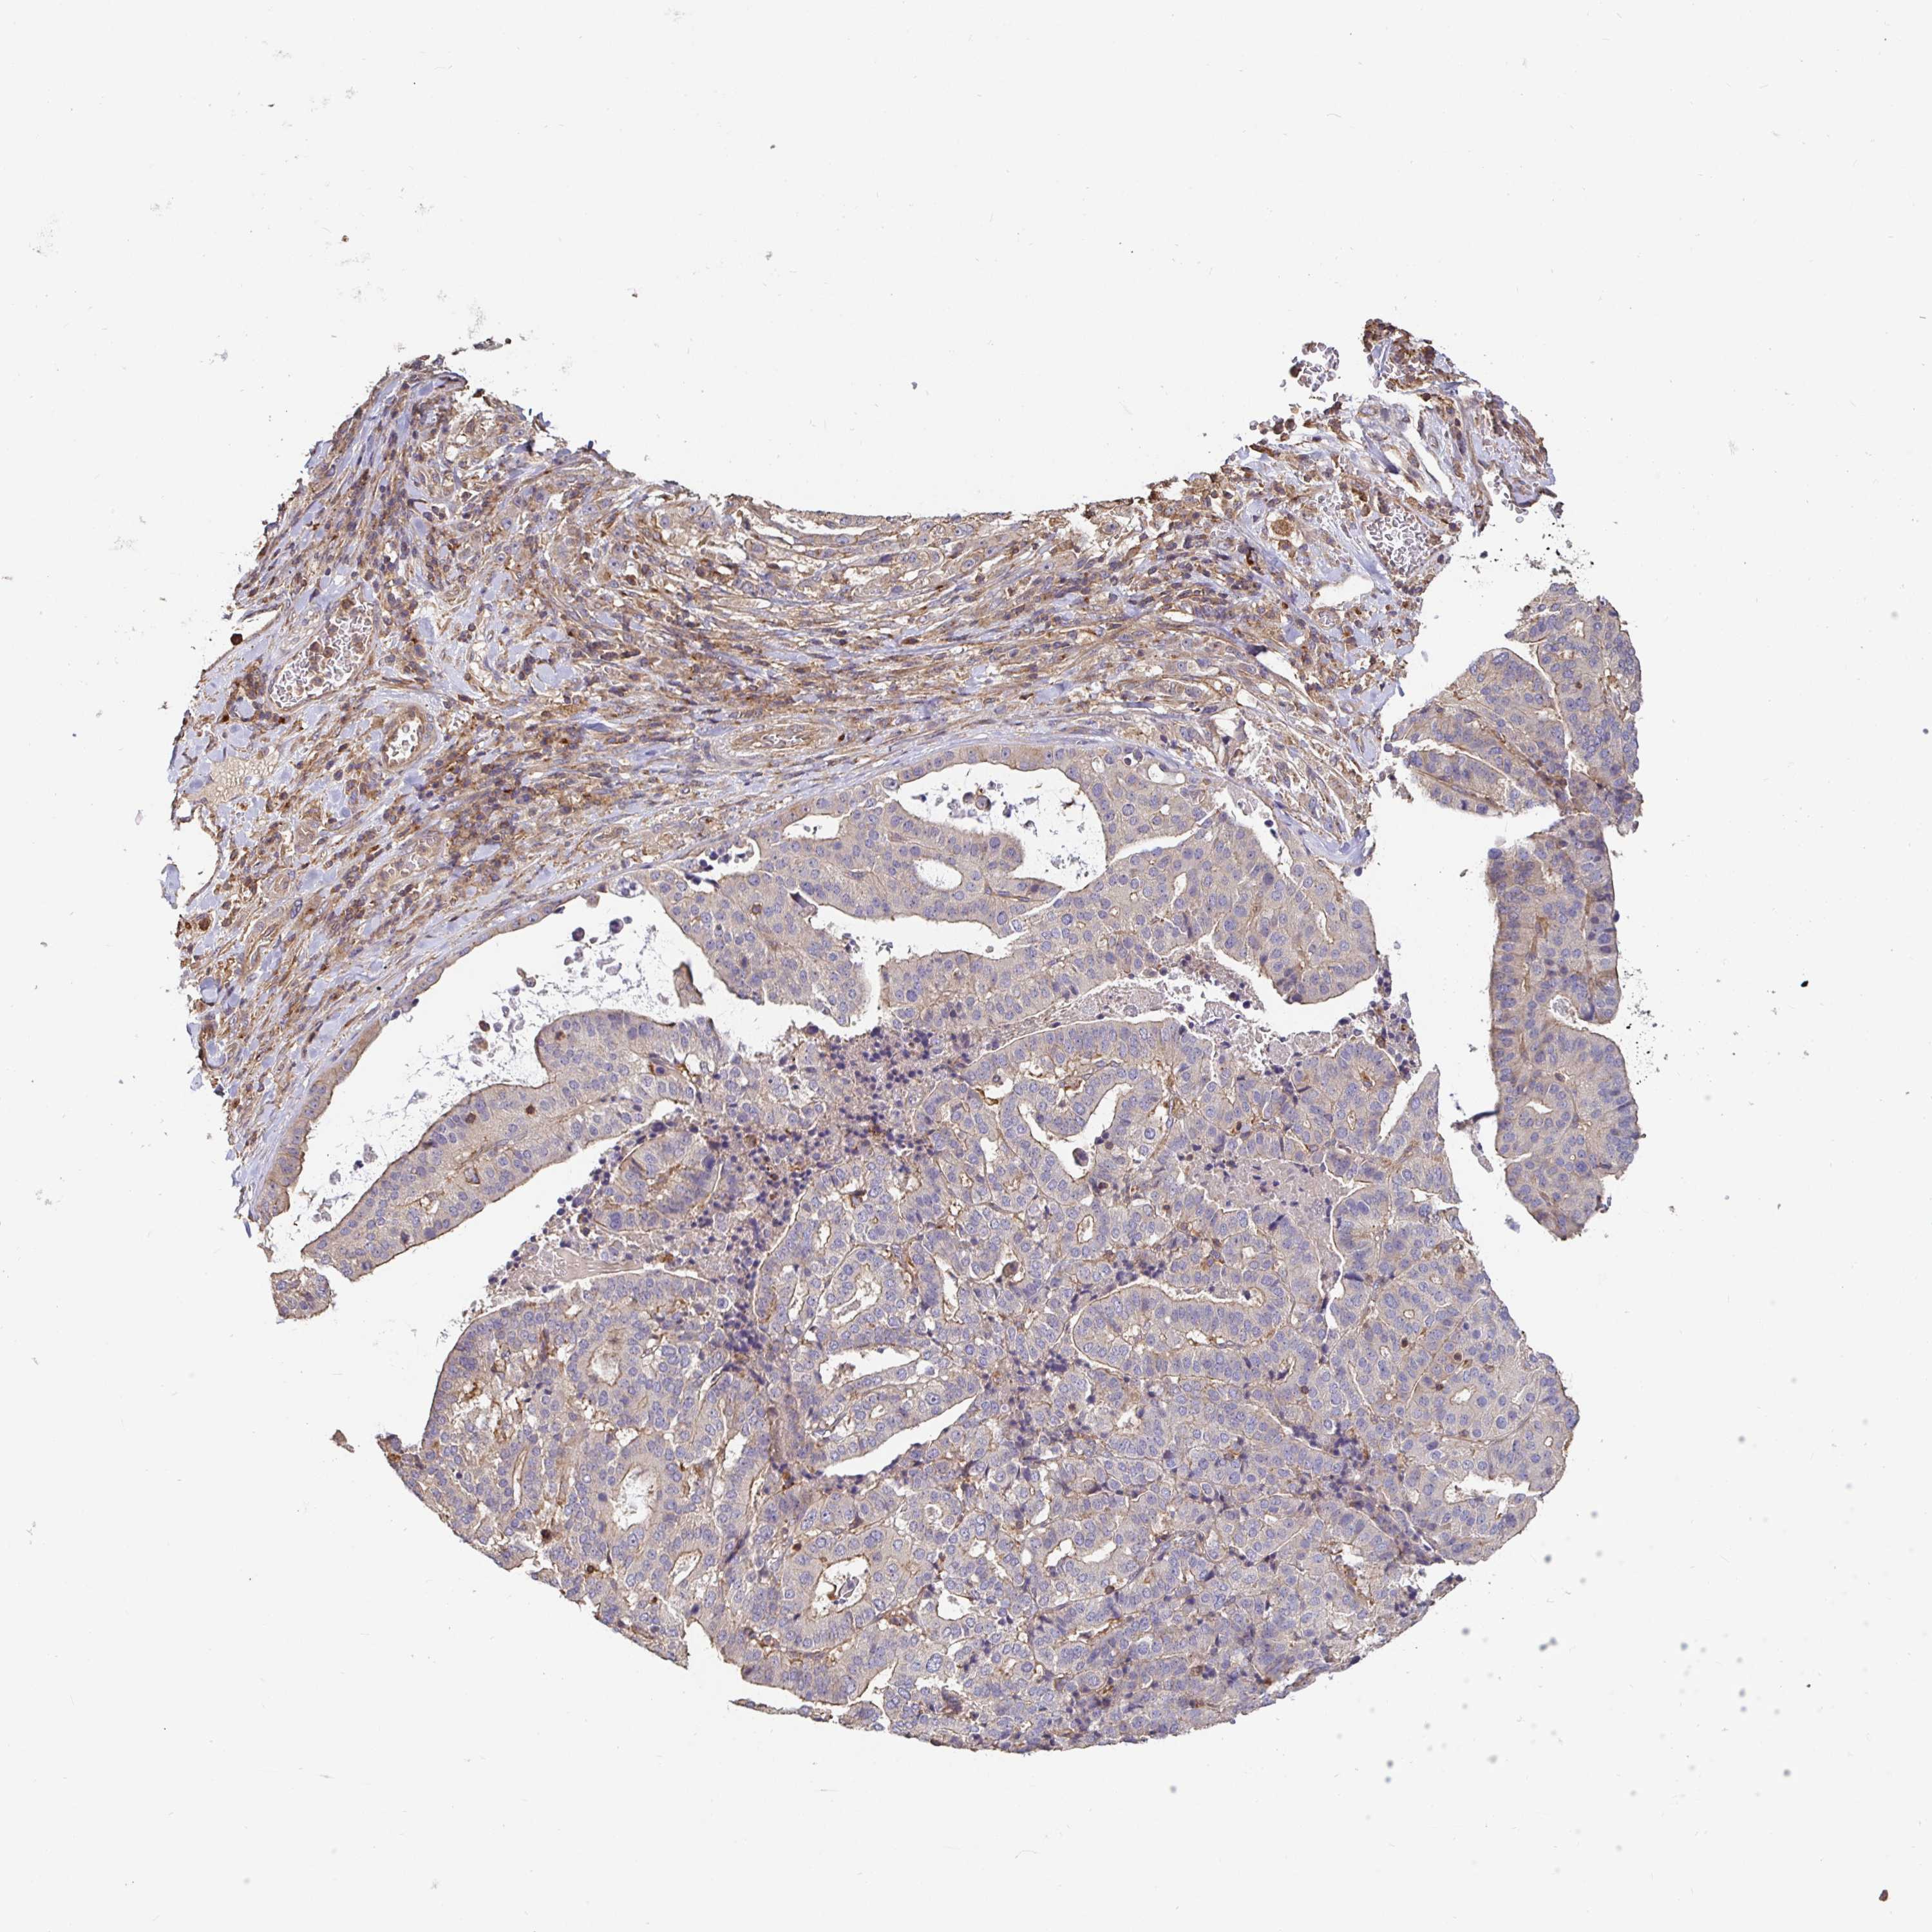

STOMACH CANCER - Protein expressioni

A mouse-over function shows sample information and annotation data. Click on an image to view it in a full screen mode. Samples can be filtered based on level of antibody staining by selecting one or several of the following categories: high, medium, low and not detected. The assay and annotation is described here.

Note that samples used for immunohistochemistry by the Human Protein Atlas do not correspond to samples in the TCGA dataset.

Antibody stainingi

Antibody staining in the annotated cell types in the current human tissue is reported as not detected, low, medium, or high, based on conventional immunohistochemistry profiling in selected tissues. This score is based on the combination of the staining intensity and fraction of stained cells.

Each image is clickable and will lead to virtual microscopy that enables deeper exploration of all samples and also displays staining intensity scores, fraction scores and subcellular localization as well as patient and tissue information for each sample.

Antibody HPA051797

Antibody CAB007055

Staining

High

Medium

Low

Not detected

Intensity

Strong

Moderate

Weak

Negative

Quantity

>75%

75%-25%

<25%

None

Location

Nuclear

Cytoplasmic/membranous

Cytoplasmic/membranous,nuclear

Adenocarcinoma, NOS

Adenocarcinoma, High grade